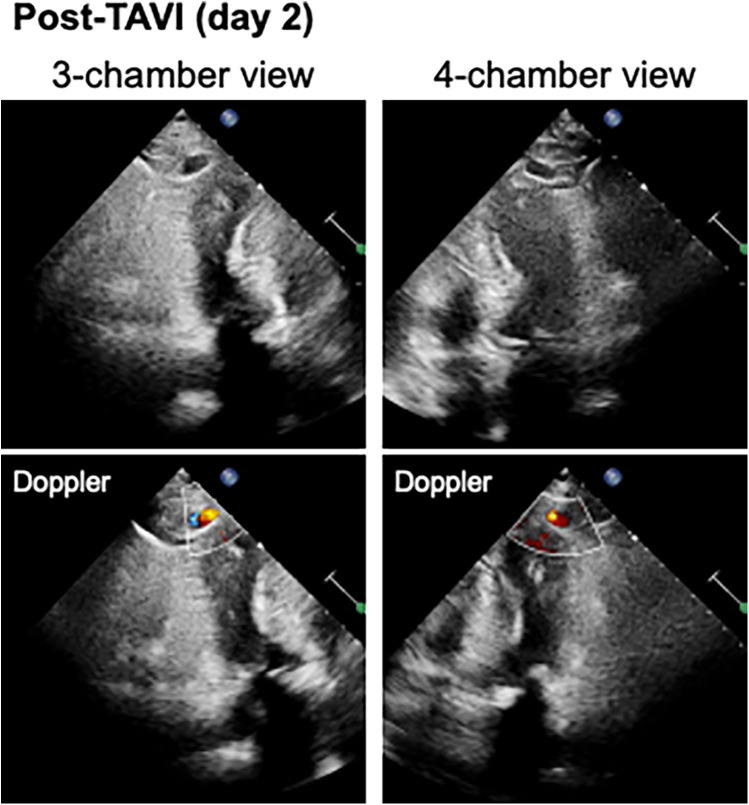

经导管主动脉瓣植入术(TAVI)最近成为手术主动脉瓣置换术的一种微创替代方法。然而,它仍然与潜在的危及生命的并发症有关。其中,左心室假性动脉瘤是一种罕见但严重的事件。虽然很少报道,但它的发生可能伴随着快速的临床恶化和致命的结果。我们报告一例84岁妇女严重主动脉狭窄(AS),谁发展左心室假性动脉瘤后TAVI。术前超声心动图显示主动脉瓣严重钙化且不动,峰值流速为4.0 m/s,主动脉瓣面积为1.17 cm²,平均压力梯度为38 mmHg。选择了一种自膨胀阀来优化环空上部署。手术后一天,影像学显示左心室顶端有假性动脉瘤。本病例强调了TAVI罕见但关键的并发症。我们讨论了此类事件的潜在机制、预防措施和管理策略。

Transcatheter aortic valve implantation (TAVI) has recently become a minimally invasive alternative to surgical aortic valve replacement. However, it remains associated with potentially life-threatening complications. Among these, left ventricular pseudoaneurysm is a rare but serious event. Although infrequently reported, its occurrence may be followed by rapid clinical deterioration and fatal outcomes. We report the case of an 84-year-old woman with severe aortic stenosis (AS), who developed a left ventricular pseudoaneurysm following TAVI. Pre-procedural echocardiography showed a heavily calcified and immobile aortic valve, with a peak velocity of 4.0 m/s, an aortic valve area of 1.17 cm², and a mean pressure gradient of 38 mmHg. A self-expandable valve was selected to optimize supra-annular deployment. One day after the procedure, imaging revealed a pseudoaneurysm at the left ventricular apex. This case highlights a rare but critical complication of TAVI. We discuss potential mechanisms, preventive considerations, and management strategies for such events.